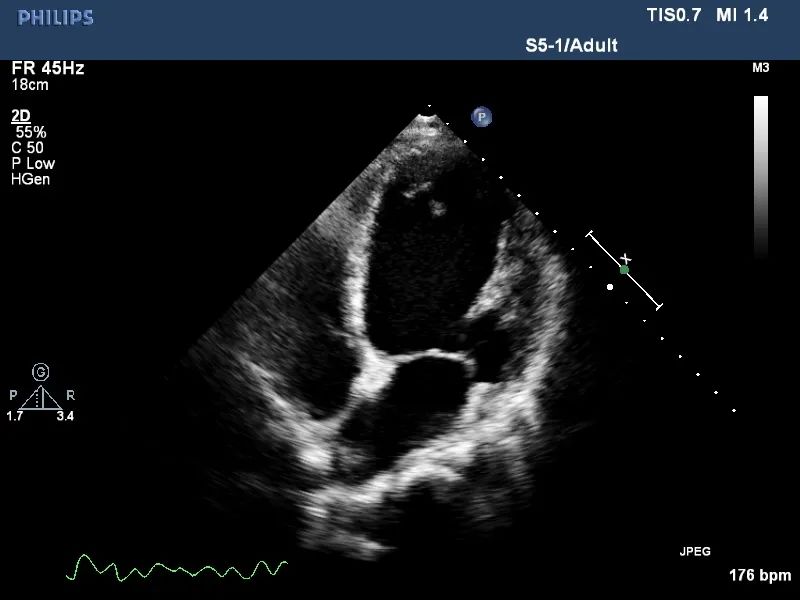

术后超声

手术用时1小时15分钟,术中采用10mm球囊预扩张房间隔,并植入8mm孔径心房分流器。术后左心房压力下降,患者胸闷气短症状明显好转,次日患者即可下床活动,术后5天复查各类指标且康复良好,顺利出院。